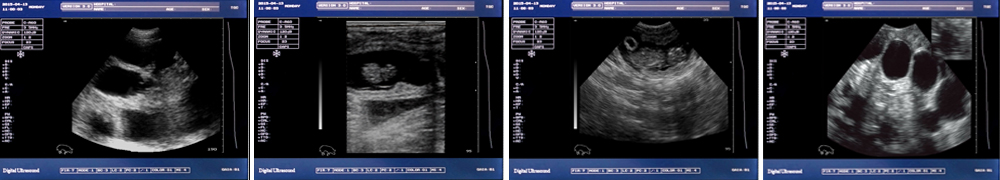

一流的數(shù)字成像技術(shù),圖像更清晰